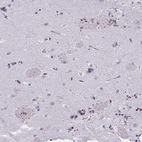

Immunohistochemical staining of human caudate shows strong dot-like positivity.